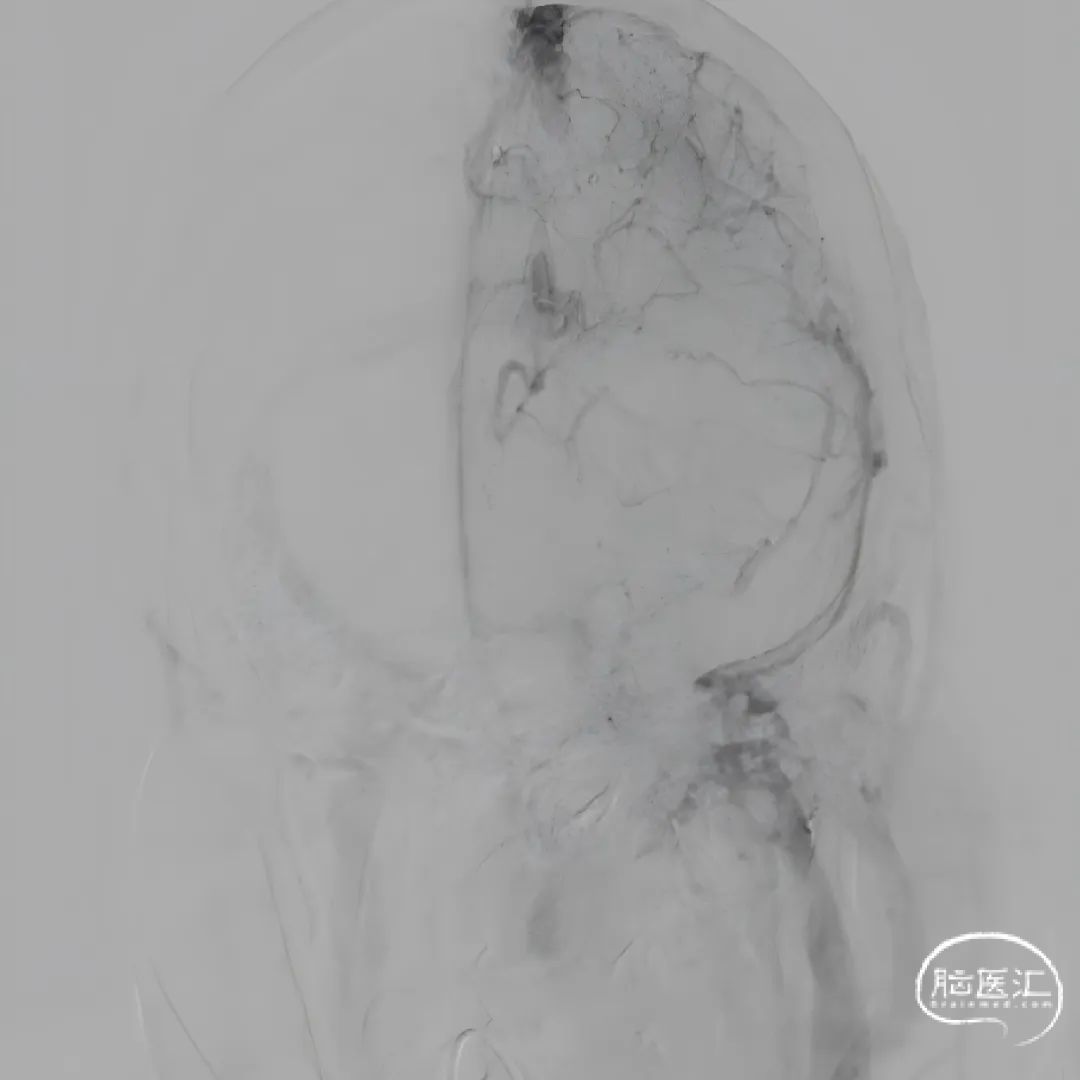

球扩后造影,上矢状窦接触溶栓尿激酶20万U。

球囊扩张和接触溶栓后,再次经中间管反复抽吸后复查造影。

再次给予尿激酶10万U后复查造影。

再次给予球囊扩张,球扩后复查造影。